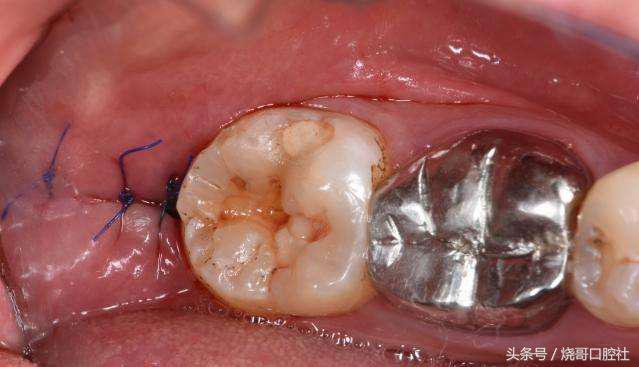

拔牙后是可以不用拆线的!比如羊肠线可以免拆,自动被牙龈组织吸收,但普通缝合线不可吸收,一般在5~7天内进行拆线处理,如果不及时拆线,要注意缝合线和牙龈长在一起,细菌会刺激牙龈发炎红肿,甚至引起口腔溃疡。

2、不管拔牙部位在前牙还是后牙,拔牙窝恢复后再镶牙或种牙已经失去意义,要知道镶牙和种牙最怕的就是牙周炎,就像土壤都没有了,怎么固定住牙根?

3、如果创口是智齿位置,那有可能会引起干槽症,明显拔牙后3~4天创口痛感会更加强烈,而且缝合线附近溃疡有异常的暗灰色,有时还能感觉到臭味。